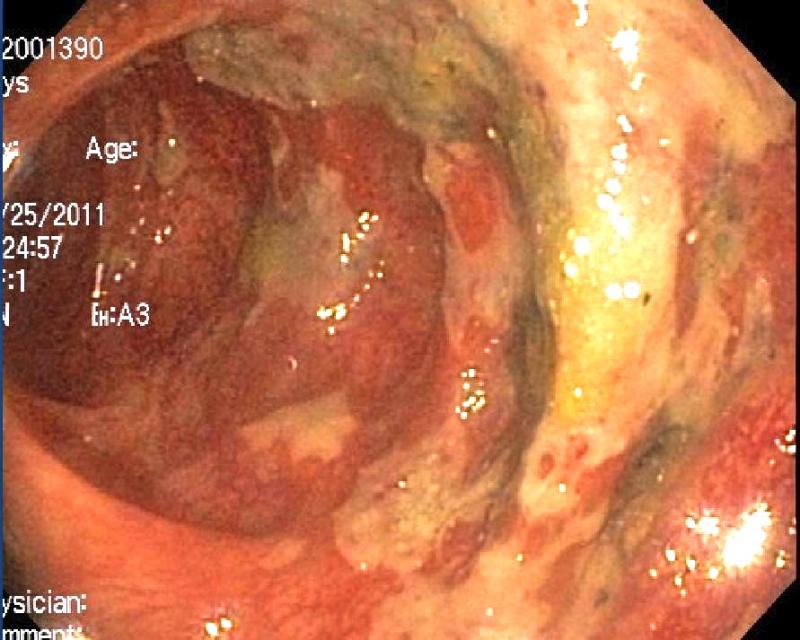

An 61 year old patient had urinary tract infection. He received antibiotic therapy. He presented later with diarrhea. Colonoscopy was done photograph is given below. What is the Diagnosis?

Answer is c) Pseudomembranous colitis

This is classical appearence on colonoscopy. The classic appearance of 2-mm to 10-mm raised yellow nodules is pathognomonic. These lesions are usually discrete but may become confluent plaques in more advanced cases. Usually colonoscopy is not done as it is invasive procedure. Diagnosis is usually made by detecting C.difficale toxins.